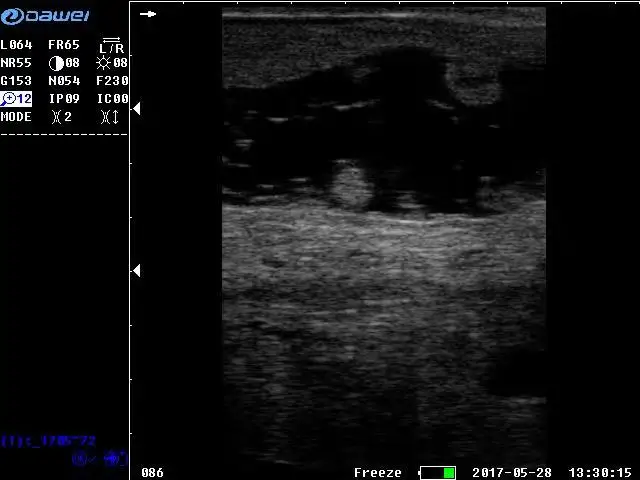

Display mode | B, 2B, 4B, B/M, M |

Frequency range | 3.5MHz(2.5/3.5/5.0), 5.0MHz(3.5/5.0/6.5), 6.5MHz(5.0/6.5/7.0), 7.5MHz(6.5/7.5/8.0) |

Pregnancy test | Bovine(BTD, BUD), Equine(EGSD、ESD), Swine(HLA、SLA), Ovine(SCRL), Canine(HD、BD、GSD、CRL), Feline(HD、BD) |